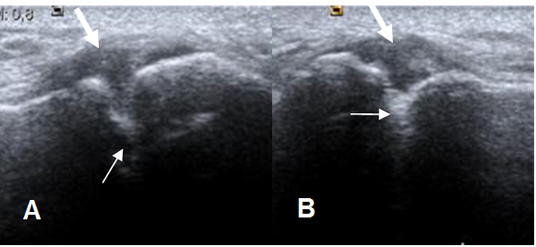

Fig 83. Cambios degenerativos en articulación acromioclavicular.

A y B: Ecografía coronal. Osteofitos en la articulación acromioclavicular (Flechas delgadas), con la presencia de líquido (Flechas gruesas) por cambios degenerativos.